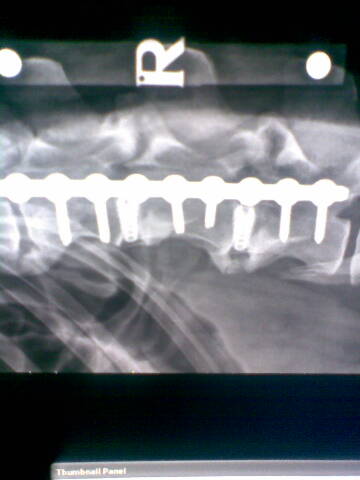

It was make or break. Noel said he could attempt something that had never been done before, the separating of discs from each other and the spinal chord via several screws inserted at a specific angle. These would give the spinal chord the room it needed to recover, or at least give it a better chance, although the procedure was a potentially a highly dangerous one and one that to Noel's knowledge had never been carried out before.

For those of you who are intrigued here's the actual miracle in place. Amazing, amazing people who do these things.